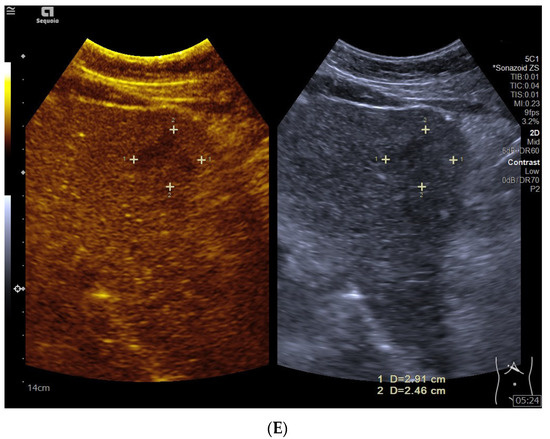

フィリップス、「Liver Fat Quantification(肝脂肪化定量評価。肝臓がん|消化器|診療内容|医療法人 甘木第一クリニック。肝臓がん|消化器|診療内容|医療法人 甘木第一クリニック。sakuraさん専用 蔵王吊るし柿4kg 紅干し柿 600g。Contrast Enhanced Ultrasound (CEUS) | フィリップスヘルスケア。Liver Ultrasonography | SpringerLink。キヤノンメディカルシステムズ、『肝臓の脂肪量の汎用超音波画像。Imaging Features of Hepatocellular Carcinoma in the Non。Imaging Features of Hepatocellular Carcinoma in the Non。714cFtk9QyL._AC_UF350,。肝臓病変における超音波の最新情報-第24回腹部放射線研究会。KMS_M01_XXX_670.jpg。腹部の超音波検査健康なヒト胆嚢 - 胆嚢のストックフォトや画像。